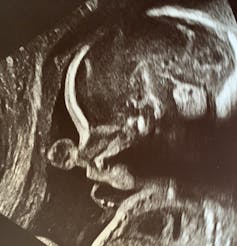

The large brains, relative to overall body size, that are a defining characteristic of our species make pregnancy and gestation particularly interesting to paleoanthropologists like me. Homo sapiens’ big skulls contribute to our difficult labor and delivery. But the big brains inside are what let our species really take off.

But human pregnancy, and particularly labor and delivery, cost a lot of energy and are often dangerous. The large fetal brain requires a lot of nutrients during development. The rate of embryonic growth during gestation, also known as the prenatal growth rate, exacts a metabolic and physiological toll on the gestating parent. And the tight fit of the infant’s head and shoulders through the pelvic canal during delivery can lead to death, for both the mother and child.

Humans have the highest prenatal growth rate of all primates living today, at 0.41 ounces/day (11.58 grams/day). Gorillas, for example, have a much larger adult body size than humans, but their prenatal growth rate is only 0.29 ounces/day (8.16 grams/day). Because more than a quarter of all human brain growth is completed during gestation, the rate of prenatal growth directly relates to how big an adult brain grows. How and when Homo sapiens‘ high prenatal growth rate evolved has been a mystery, until now.